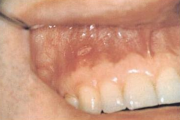

villikesest tekkinud haavand suu limaskestal